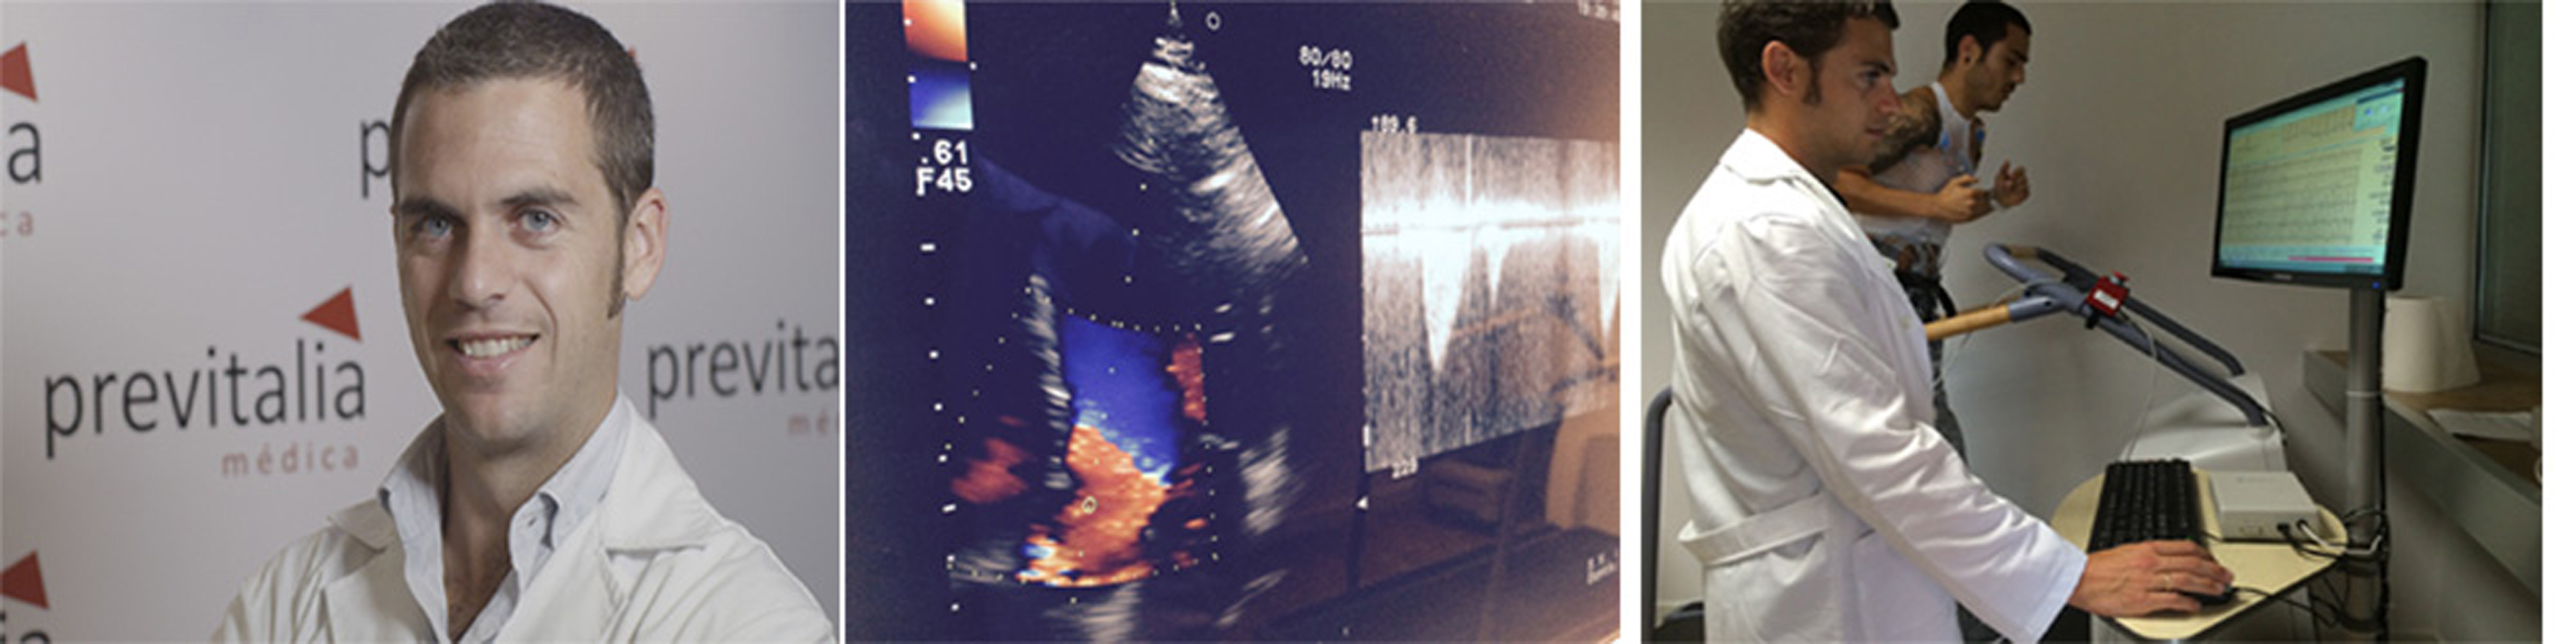

UNIDAD DE CARDIOLOGÍA AVANZADA

ecocardiografia aviles

La unidad de cardiología avanzada le proporciona uno de los servicios médicos más eficientes y completos de Asturias. Nuestros esfuerzos están encaminados a proporcionar una atención de la máxima calidad, a la vanguardia de los últimos avances y comprometido con las necesidades de atención de los pacientes y sus familias. La unidad atenderá integralmente sus necesidades para la prevención, el diagnóstico y la rehabilitación de la enfermedad cardiovascular gracias a un excelente equipo médico y una tecnología de última generación y de prestigio.

Estamos preparados para asesorarle a usted y su familia, antes, durante y con posterioridad a la asistencia médica, con flexibilidad, para facilitarle al máximo el proceso, resolviendo cuantas dudas pueda tener respecto a las diferentes opciones de diagnóstico y tratamiento existentes, proporcionándole información completa sobre cuál es la más adecuada para usted. Nuestro personal le acompañará durante todo el proceso y se ocupará de las cuestiones burocráticas y administrativas si las hubiere, para que nada interfiera en su atención médico sanitaria.

No dude en consultar de manera gratuita cualquier cuestión relativa a su salud cardiovascular. Estaremos encantados de atenderle. Leer más...